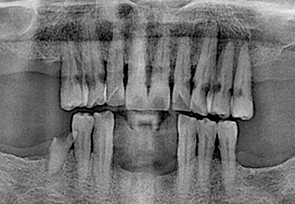

before

after